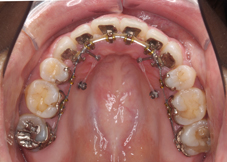

左:歯の移動開始時 - 装置装着時、前歯で噛めない噛み合わせの状態

右:矯正治療終了時 - 歯を抜かないで治療しました。

左:治療前 右:治療後(非抜歯)

右写真は治療が終了して装置を外した時のものです。写真の使用に際して快く承諾して頂いたnaokoさんありがとうございます。

MEAW(マルチループワイヤー)で治療しました。MEAWを使用すると診断によっては歯を抜かないで噛み合わせを改善できることがあります。

右:矯正治療終了時 - 歯を抜かないで治療